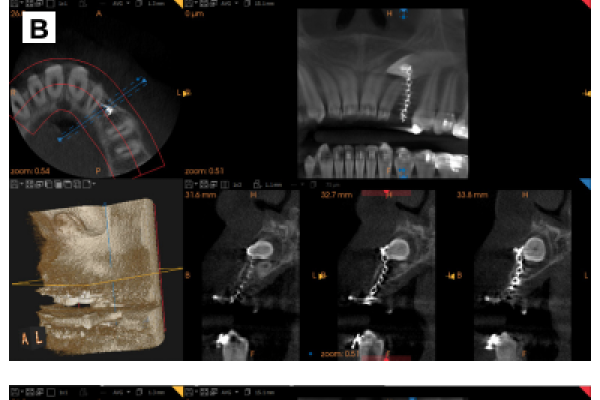

Manejo integral quirúrgico y ortodóntico del autotrasplante de un canino incluido en maxilar. A propósito de un caso